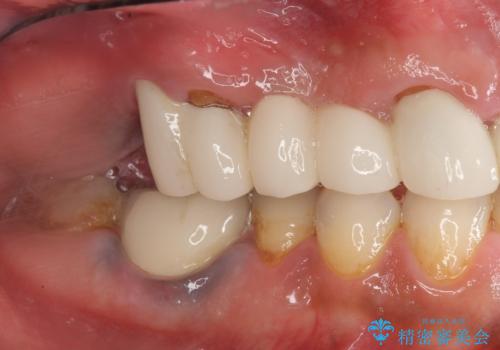

- 歯が疲れるとうずき、気持ちが悪い、しっかりと噛めない気がする。と改善を求めて来院されました。

数年前にセラミック歯を入れたが、調子が悪いので今回は根本的にしっかりと治したい。とも希望されました。

X線写真検査より、根尖病変に加え、歯周病による歯槽骨の吸収も見られ、歯質も薄く保存は難しいと判断し、

インプラント治療を進めることとなりました。